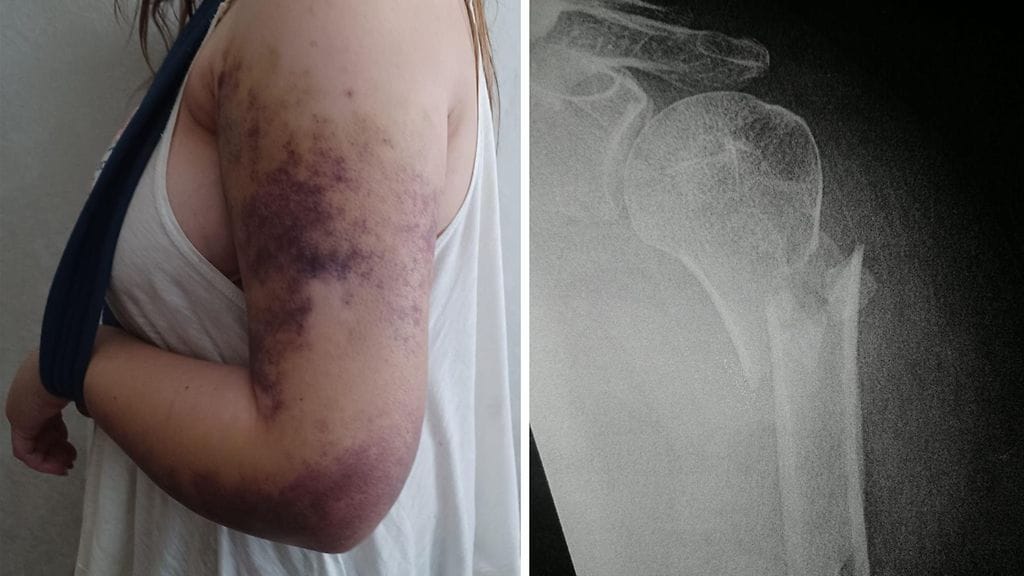

Hän meni samana päivänä Kuopion yliopistolliseen sairaalaan (KYS), jossa hänellä diagnosoitiin olkaluun yläosan pirstaleinen murtuma. MTV Uutiset on nähnyt hänen potilaskertomuksensa.

– Käsi on pikimusta olkapäästä lähes kämmenselkään asti ja todella kipeä, Riikka sanoo.

– Kipu on aivan kokoaikaista.